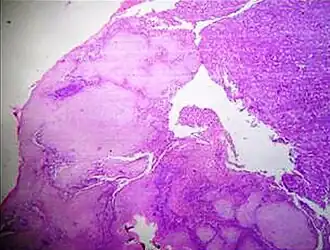

A crush artifact is an artificial elongation and distortion seen in histopathology and cytopathology studies, presumably because of iatrogenic compression of tissues. Distortion can be caused by the slightest compression of tissue and can provide difficulties in diagnosis.[2][3] It may cause chromatin to be squeezed out of nuclei.[4] Inflammatory and tumor cells are most susceptible to crush artifacts.[4]